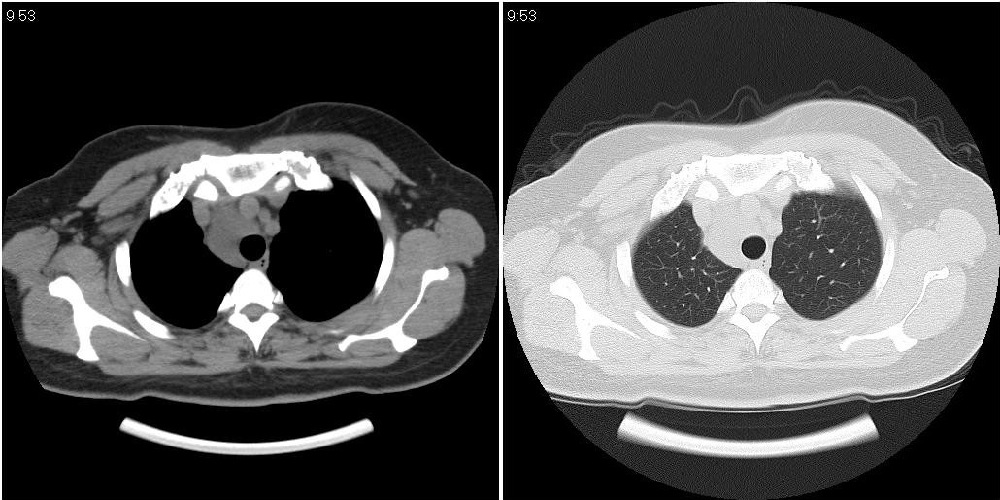

标题: CT24795:女性,47岁,右下腿静脉静脉曲张手术前体检,发现 [打印本页]

标题: CT24795:女性,47岁,右下腿静脉静脉曲张手术前体检,发现

囊性无明显占位效应:1淋巴管囊肿2畸胎瘤(其上部见小钙化)3前肠囊肿

右上纵隔囊性占位性病变;考虑淋巴管囊肿,不排除支气管囊肿。

支气管囊肿、囊性畸胎瘤、肠源性囊肿均有可能。

右上纵隔囊性占位性病变;考虑淋巴管囊肿,不排除支气管囊肿。 建议增强。

考虑淋巴管囊肿,不排除前肠囊肿。